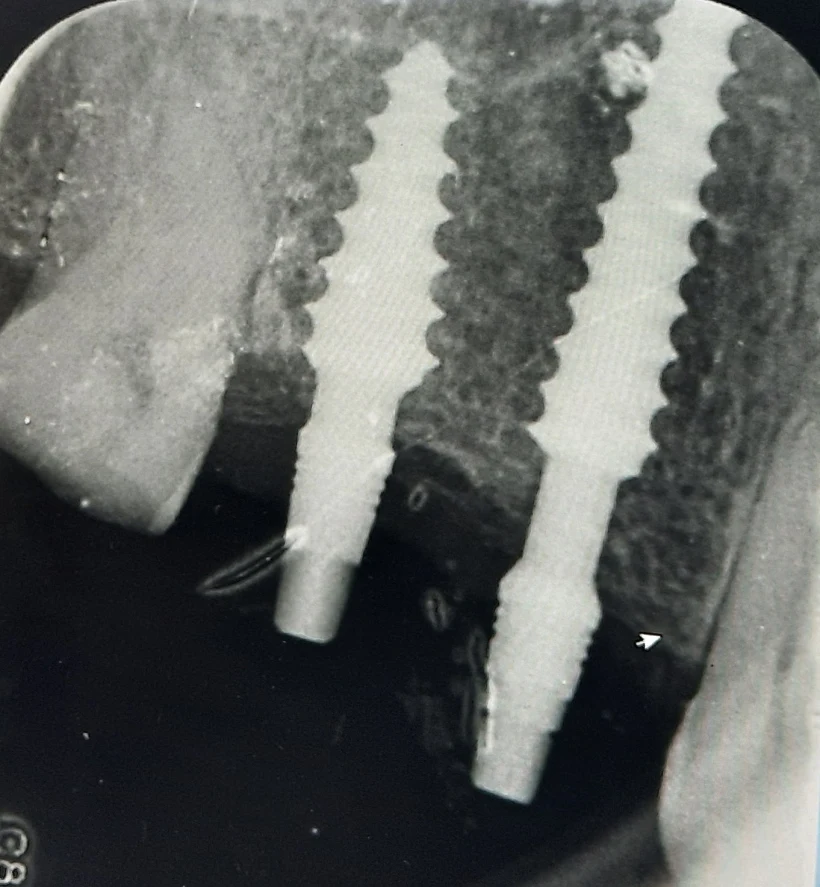

ד"ר עמאשה הוא בעל תואר D.M.D, בעבר היה מרצה מרצה מטעם החברה לטכנולוגיה רפואית חדשנית " ,"Green Implantכאשר ערך עבורה גם מחקרים קליניים בתחום השתלים הדנטליים.

כיום, במקביל לפעילותו במרפאות הרשת, הוא משמש כמרצה ומדריך ב"המכללה למדעי הבריאות וההתנהגות", מכהן כמדריך בחברה השוויצרית לשתלים “”SGS והוא חבר בעמותה הבינלאומית למשתילים.

*המרפאה מבצעת השתלות שיניים, קומפרסיבים והעמסה מיידית בשיטה חדשנית, כולל שיקום תוך שבוע ימים.

*השתלות שיניים ביום אחד, גם למי שסובל ממחסור בעצם, כאשר ישנה אחריות מלאה על השתלים ועל הטיפולים.